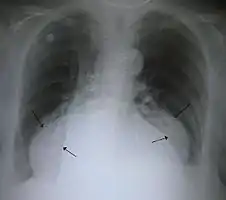

A large hiatal hernia on chest X-ray marked by open arrows in contrast to the heart borders marked by closed arrows

This hiatal hernia is mainly identified by an air-fluid level (labeled with arrows).